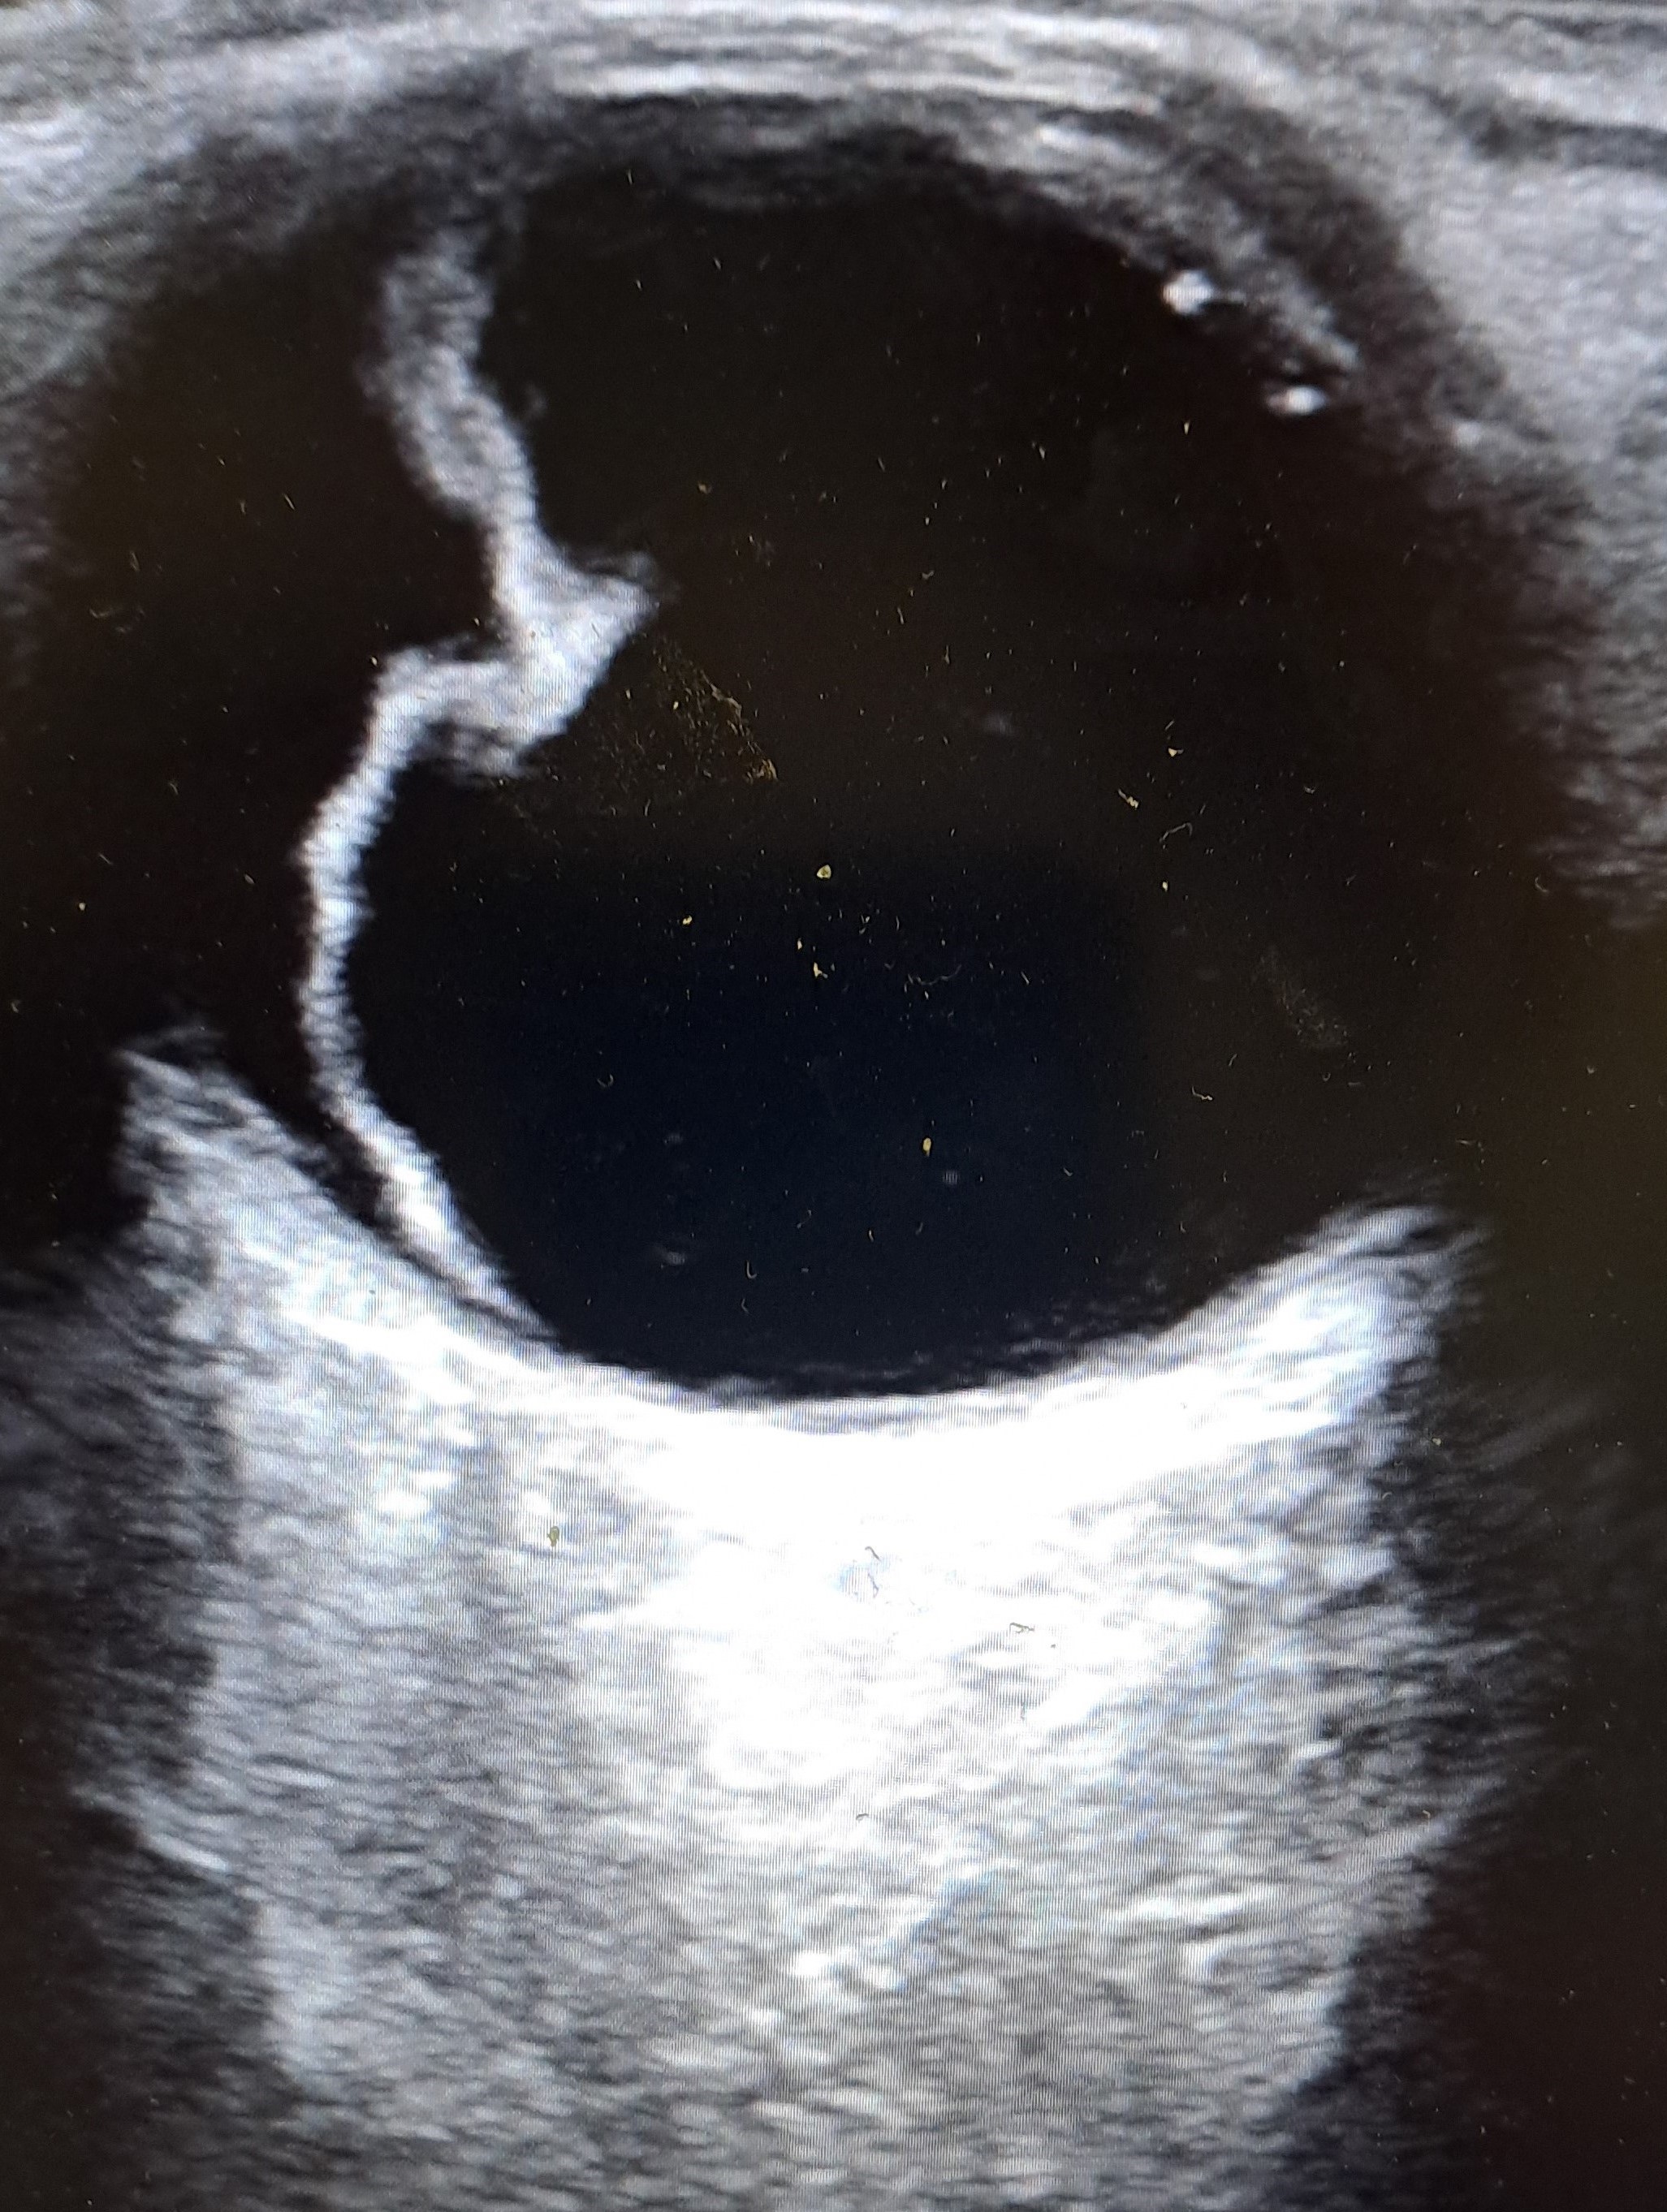

Se realiza ecografía clínica para valoración de ojo derecho.

Se realiza ecografía clínica objetivando línea hiperecogénica en región temporal-central del ojo derecho a la altura del humor vítreo.

Desprendimiento de retina extensa en región temporal en ojo derecho.